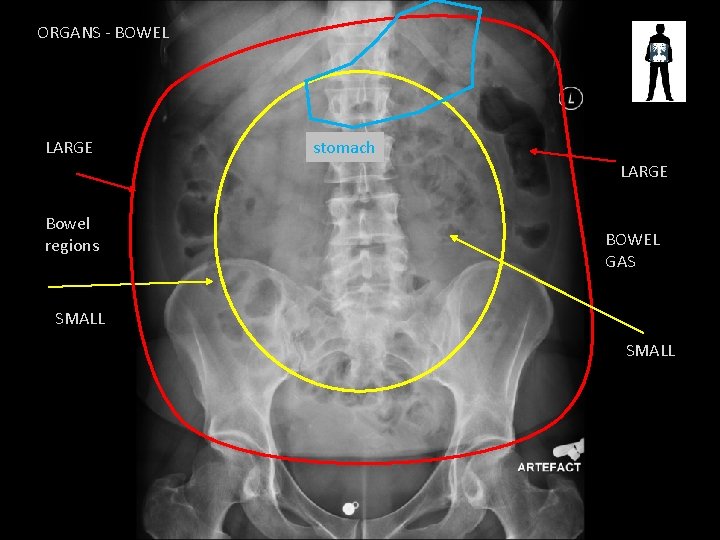

ORGANS - BOWEL LARGE stomach LARGE Bowel regions BOWEL GAS SMALL